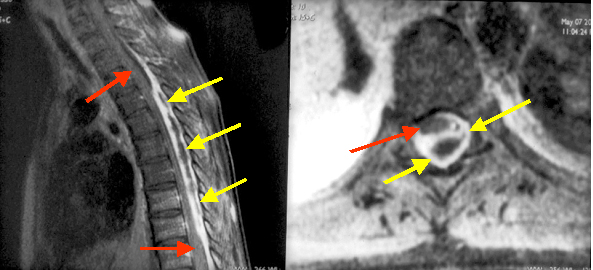

Epidural abscessThe central portion of the midthoracic cord is compressed and displaced anteriorly (red arrows in A outline the thoracic cord both above and below the level of cord compression) by an epidural abscess (yellow arrows in A, B). The capsule of the abscess enhances intensely with central low signal intensity produced by pus. Figure B demonstrates ventrally displaced thoracic cord (red arrow) by dorsally located epidural abscess (yellow arrows) |

| Post contrast sagittal T 1 wtd. MRI of the thoracic spine I | Post contrast Axial T 1 wtd. MR |